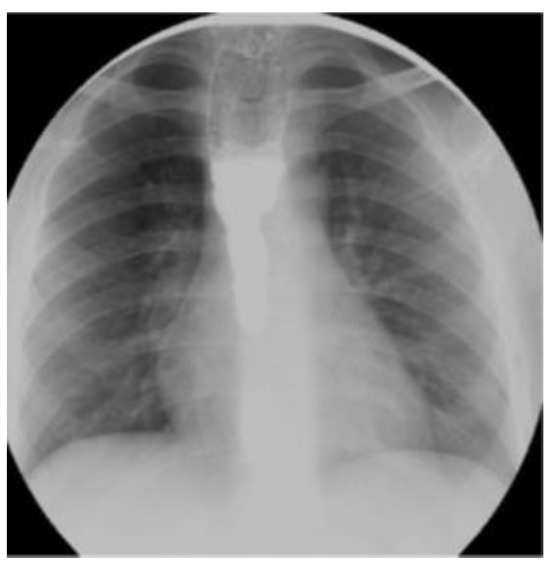

A Pedunculated Esophageal Chondromatous Hamartoma in a Child

Case Report